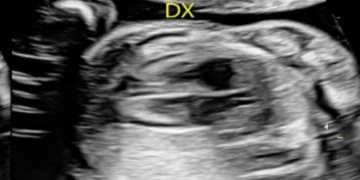

Guida al Counselling di Maggio 2025: patologie cistiche della fossa cranica posteriore

Cari colleghi, vi presentiamo la guida al counseling di Maggio 2025 sulla Patologia cistica della fossa cranica posteriore. Potrete scaricarla cliccando sul link. Grazie a Laura Sarno! ...